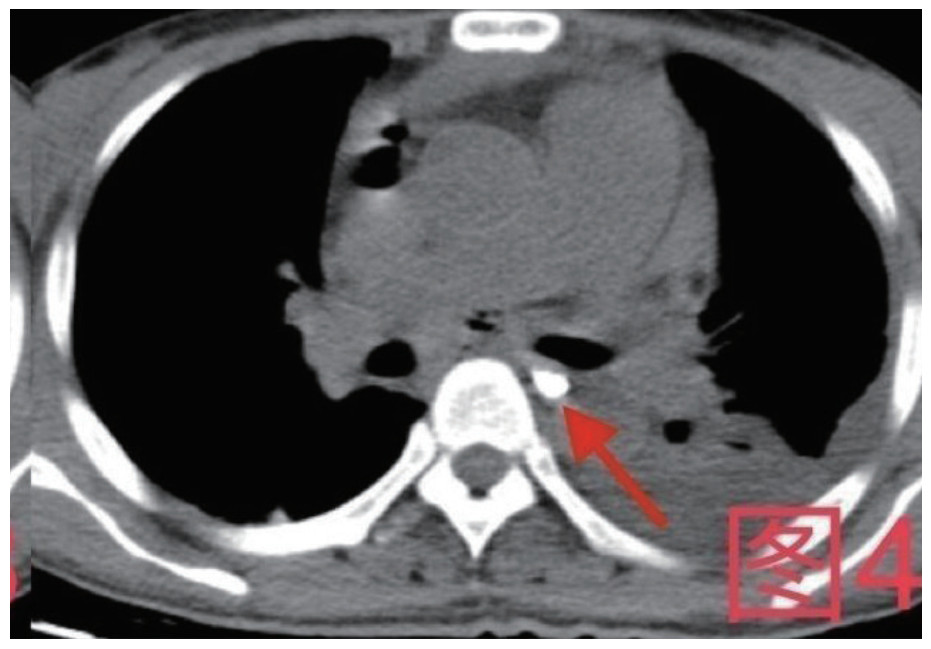

治疗经过:急诊予美罗培南0.5 g,1次/12 h抗感染,补液支持,心包引流等治疗措施,收住感染科后继续抗感染治疗,期间心包积液培养出白假丝酵母菌,加用氟康唑200 mg,1次/d, 口服,心包积液、左侧胸腔积液引流等措施,治疗10 d后复查胸部CT仍有中大量心包积液伴少许积气,纵隔积气;左侧少量胸腔积液,两肺叶间裂少许积液。对照前片(2020.10.26)心包积气及左侧胸前积液有增多,叶间裂积液新发,心包积液略有减少。右肺下叶感染,左肺下叶膨胀不全,较前右肺下叶感染有吸收,左肺下叶膨胀不全新发。考虑不能排除食管纵隔瘘,予口服碘海醇后胸部CT检查(图 3~6):约胸6椎体水平食管纵隔瘘,瘘口为相应水平食管壁右前方可能;胃镜(图 7):食道距门齿25 cm右后壁见一直径约1.0 cm凹陷,内有一小瘘口。胃镜下予钛夹2枚夹闭瘘口(图 8),同时植入空肠营养管。至此患者病情明确诊断食管心包瘘,患者经以上治疗后心包积液、胸腔积液逐渐减少,于11月13日拔除心包及胸腔引流管,因患者签字回当地就诊,予口服莫西沙星、氟康唑带药出院,出院后随访,患者未回当地医院治疗,仅在家中继续空肠营养管饲喂及口服抗菌药物治疗。

图 4 患者卧位第一次口服15 mL碘海醇后,箭头所指为食管内碘海醇,未见食管内碘海醇漏出